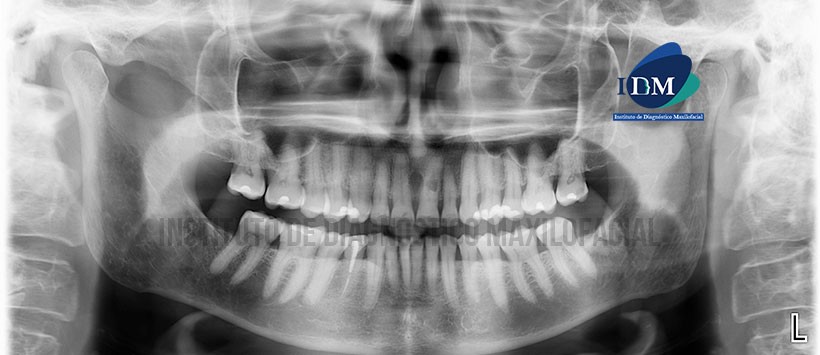

Paciente femenino, 74 años de edad, es referido al Instituto de Diagnóstico Maxilofacial (IDM) para evaluación tomográfica por presencia de imagen radiolúcida en zona radicular de pieza 2.1

En la radiografía panorámica (Figura 1) se observa leve facetamiento de los contornos condilares; remanentes radiculares de pieza 38; pieza 44 restauraciones coronarias, espigo y obturación de conductos; presencia de imagen radiolúcida proyectada a nivel del tercio medio radicular.